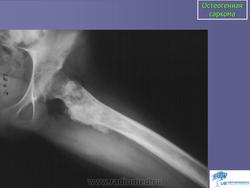

Остеогенная саркома

Рентгенологическая картина остеогенной саркомы отличается большим разнообразием и во многом определяется морфологиче ским вариантом опухоли (остеопластическая, остеолитическая, сме шанная), локализацией и темпами роста. Наиболее характерные рентгенологические признаки проявляются при разрушении коркового слоя кости и при прорастании опухоли в мягкие ткани, т. е. уже в позднем периоде развития заболевания. При этом своеобразные из менения возникают в отслаивающемся периосте с образованием на границе дефекта коркового слоя и пораженных опухолью мягких тканей характерного «козырька» или «треугольной шпоры», распо ложенной под углом к длинной оси кости. Определенное диагно стическое значение имеет обнаружение так называемых «спикул» - реактивных костных разрастании, образующихся в мягких тканях при прорастании в них опухоли. «Спикулы» на рентгенограммах об разуют характерный радиакальный рисунок, располагаясь перпен дикулярно к длинной оси кости.

Остеоидная саркома. По частоте занимает первое место среди всех злокачественных новообразований костей, составляя, по данным разных авторов, от 30 до 80% первичных сарком скелета. Встречается преимущественно у лиц детского, юношеского и молодого возраста (10-30 лет). Несколько чаще болеют лица мужского пола. Поражает главным образом метафизы длинных трубчатых костей, составляющих коленный сустав (примерно половина наблюдений), а также плечевой кости. На первом месте стоит поражение бедренной, затем большеберцовой и плечевой костей. Реже опухоль локализуется в лопатке, костях таза, черепа и др. Главный симптом заболевания - боли, которые становятся постоянными, прогрессируют в своей интенсивности и оказываются мучительными. По мере развития процесса возникают и другие клинические признаки - припухлость, опухоль различной величины, расширение кожных вен, повышение местной температуры. Появляются хромота, иногда легкая контрактура в суставе. В некоторых случаях могут возникать патологические переломы. Для остеогенных сарком весьма характерно раннее метастазирование в легкие; метастазы в лимфатических узлах наблюдаются лишь в единичных случаях.

Рентгенологически различают три формы остеогенных сарком: остеолитическую, остеопластическую (склеротическую) и смешанную. Остеолитическая форма характеризуется появлением в кости очага деструкции различных размеров с нечеткими неровными контурами, который располагается обычно эксцентрически. На первых этапах заболевания периостальная реакция почти не выражена. В дальнейшем происходит разрушение коркового слоя, отчетливо выявляется периостальная реакция с образованием характерного периостального козырька. При остеопластической форме в очаге поражения кость неравномерно уплотнена, веретенообразно утолщена. По мере роста опухоли надкостница отслаивается и возникает периостальный козырек. Образуются игольчатые, пластинчатые, гребневидные или веерообразные периостальные разрастания (спикулы). Рост опухоли и разрушение костного вещества происходят в одинаковой степени как по длиннику, так и по поперечнику кости. Костно-мозговой канал довольно быстро выполняется опухолью, на фоне которой могут прослеживаться участки обызвествления.

Остеогенная саркома.